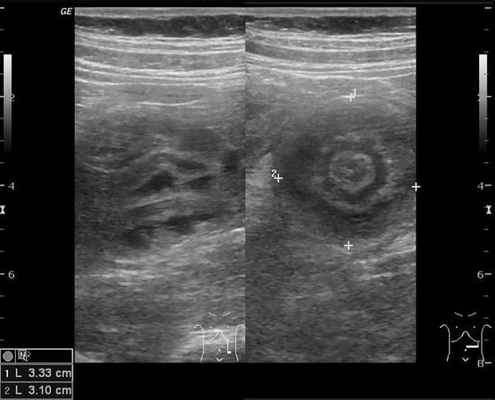

На рисунках 2 и 3 отображена ультразвуковая картина кишечной инвагинации.

Рис. 3. Симптом «псевдопочки»

В момент УЗ-исследования врач может определить один из симптомов:

- симптом мишени (за счёт внедрения одной кишки в другую инвагинат на срезе выглядит как мишень);

- симптом "почки с завоздушенным центром".